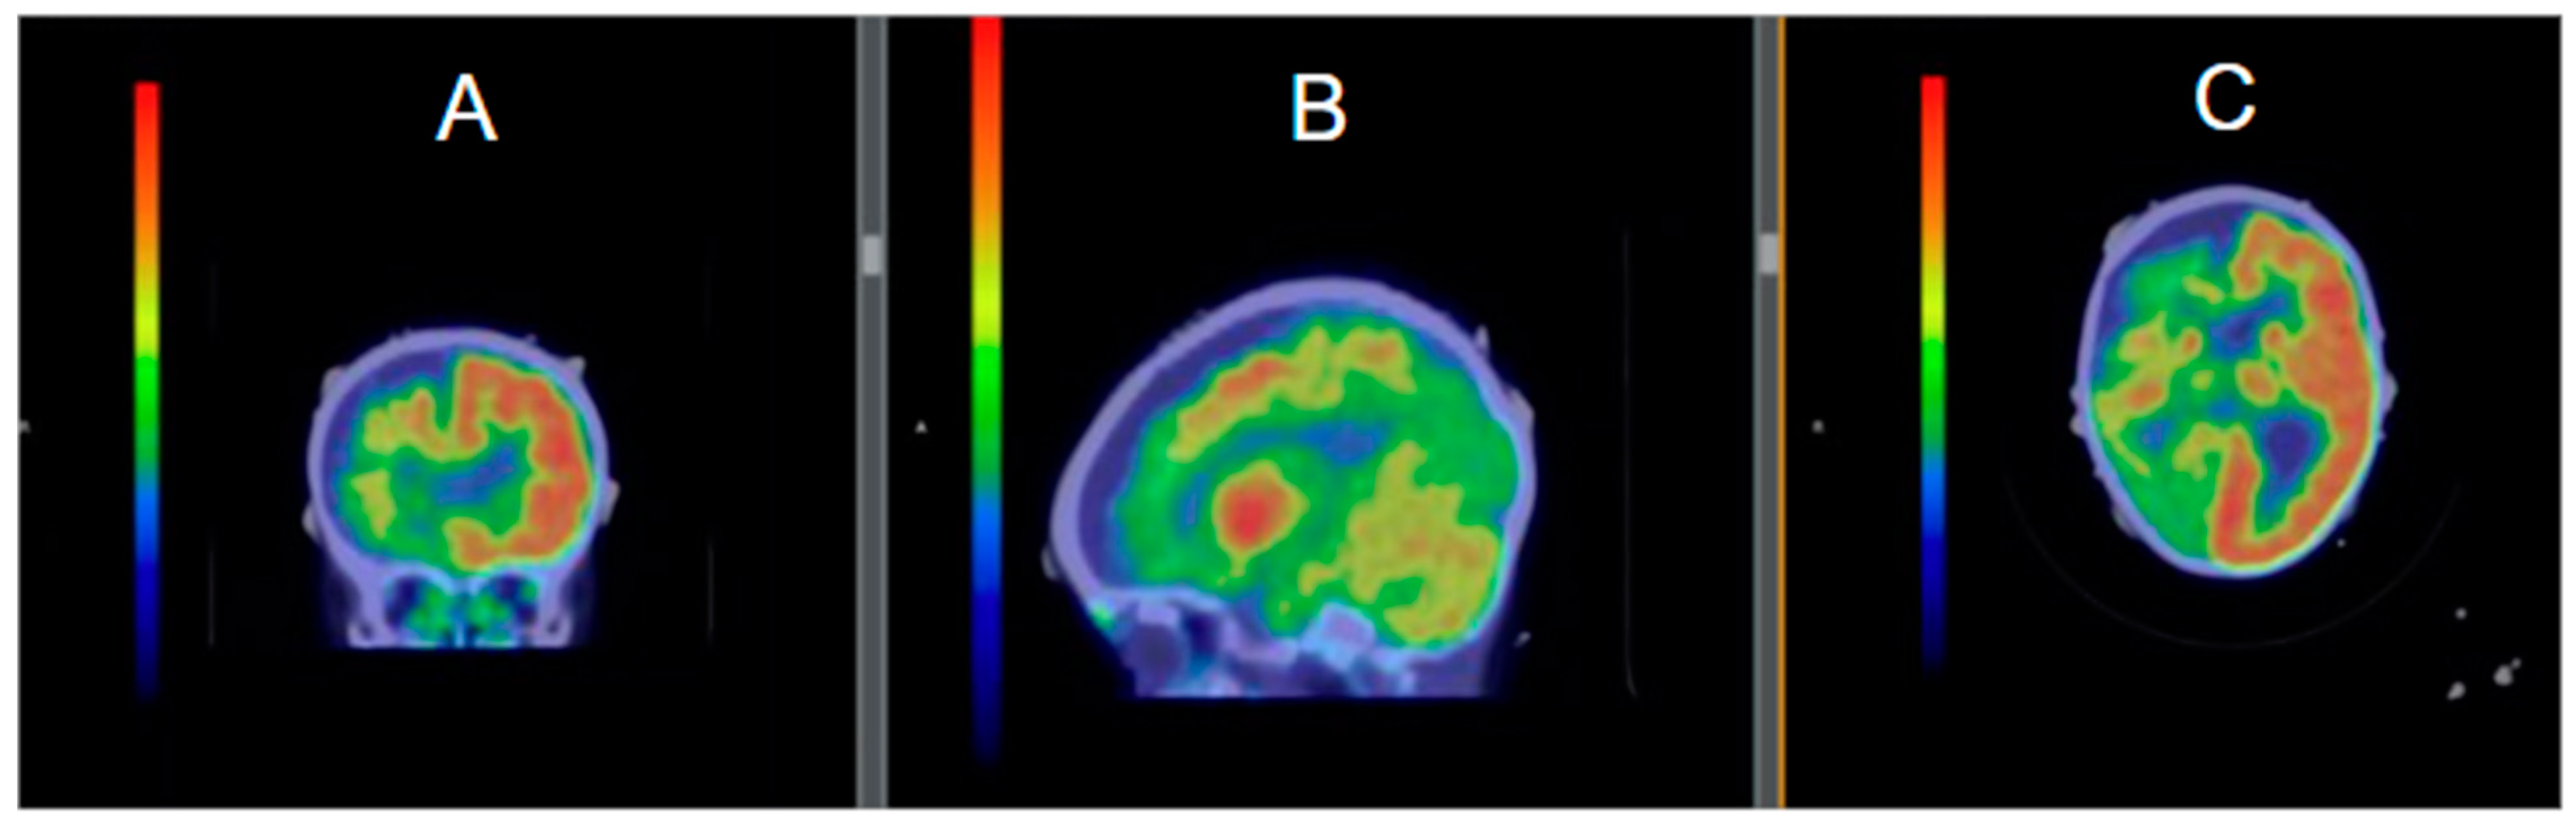

5.1. Diagnosis